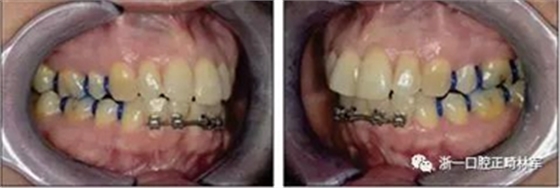

由于下頜中切牙間沒(méi)有間隙行下頜正中切開(kāi)術(shù),故進(jìn)行術(shù)前正畸擴(kuò)展間隙。下頜前牙粘托槽,中切牙托槽成交放置,將中切牙牙根分開(kāi)。使用0.018X0.018鎳鈦絲及置于下頜左、右中切牙之間的推簧推間隙。3個(gè)月后拍攝CBCT示已有足夠間隙行下頜正中截骨術(shù)。

手術(shù)前三周,上、下頜磨牙和前磨牙使用分壓圈進(jìn)行分牙。術(shù)前一天,去除下頜切牙托槽,安裝hyrax擴(kuò)弓器。